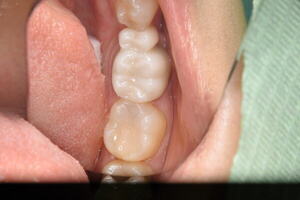

適合が悪いため、虫歯が再発 虫歯を取り除き治療終了